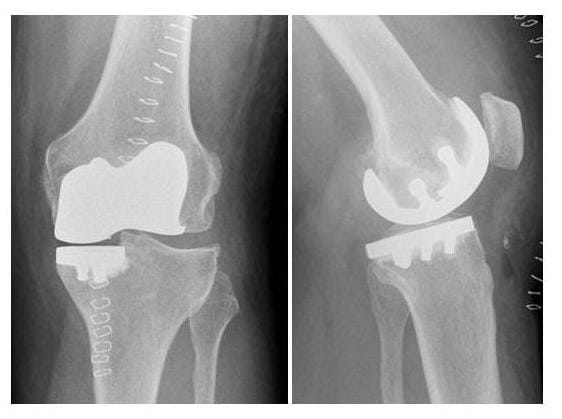

Fortgeschrittene O-Bein-Arthrose rechts mit knöchernem Defekt im innenseitigen Schienbeinbereich und 20° Streckdefizit.

Versorgung mit Roboter assistierter Knieprothese mit Ausgleich des knöchernen Defektes durch Titan-Stufe auf der Innenseite.

Digitale Prothesenplanung

Postoperatives Resultat nach Versorgung mit Roboter assistierter Knieprothese mit Ausgleich des knöchernen Defektes durch Titan-Stufe auf der Innenseite.